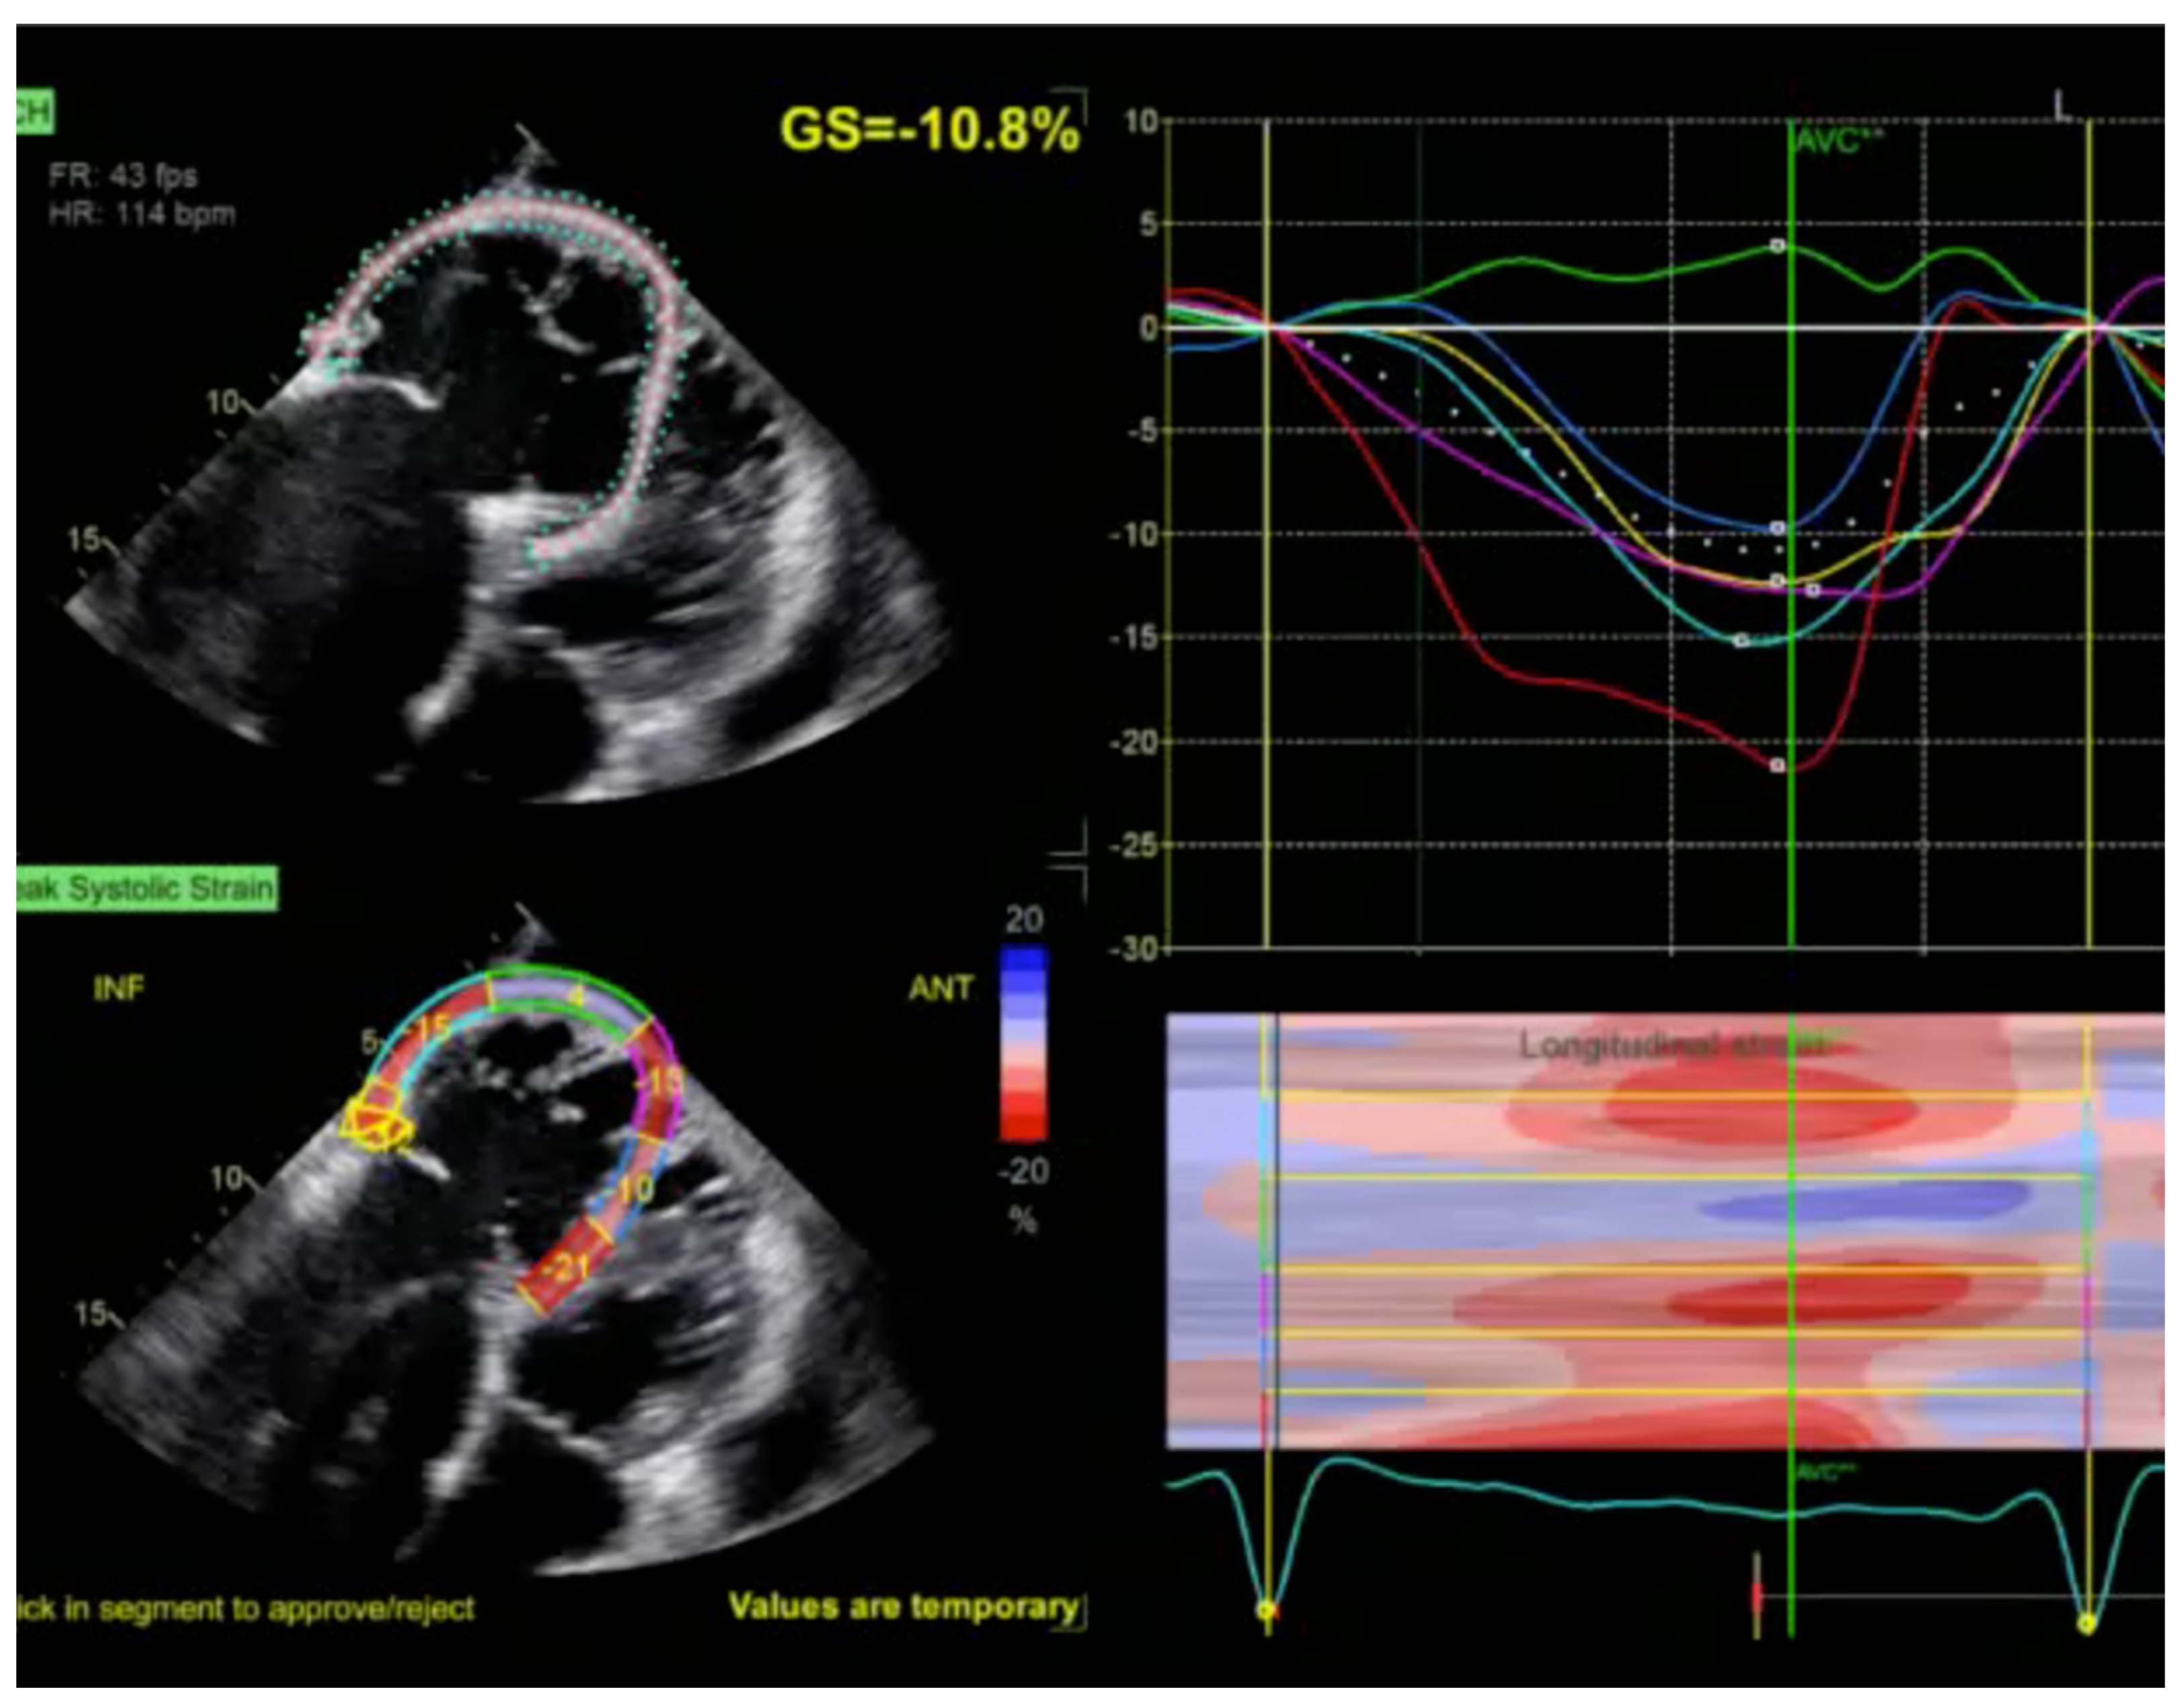

2.1. Echocardiography: The First Line of Diagnosis

5.3. Arrhythmogenic Right Ventricular Cardiomyopathy

- Gherbesi, E.; Gianstefani, S.; Angeli, F.; Ryabenko, K.; Bergamaschi, L.; Armillotta, M.; Guerra, E.; Tuttolomondo, D.; Gaibazzi, N.; Squeri, A.; et al. Myocardial strain of the left ventricle by speckle tracking echocardiography: From physics to clinical practice. Echocardiography 2024, 41, e15753. [Google Scholar] [CrossRef]